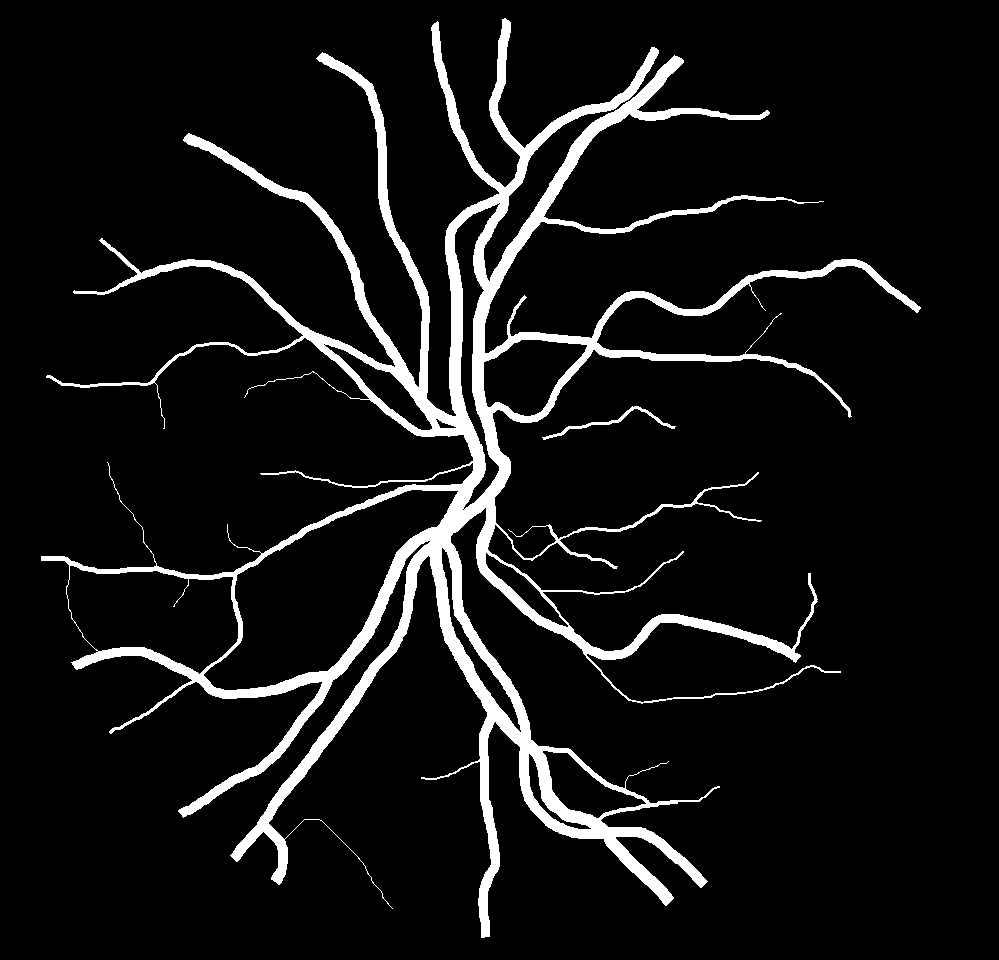

Table V presents quantitative performance benchmarks of SegRAVIR and other competing approaches for retinal artery and vein classification on the RITE dataset [11]. SegRAVIR outperforms previous state-of-the-art approaches in terms of accuracy, sensitivity, and specificity. Fig. 5 provides a qualitative comparison between segmentation outputs of SegRAVIR and the method of Hemelings et al. [40] on the RITE test set.

(a) (b) (c)